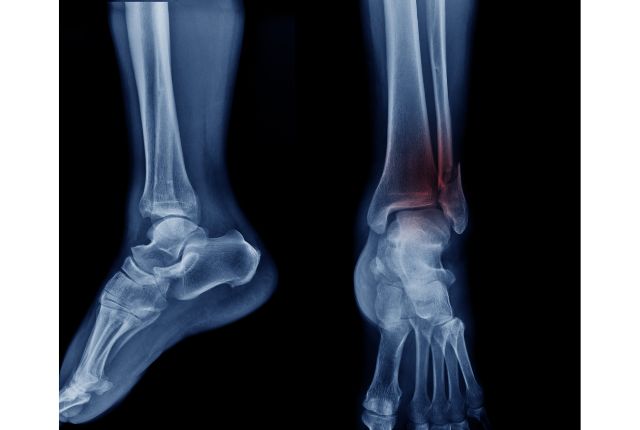

Si douleur et gonflement sont les signes cliniques d'une fracture de stress, des examens permettent de confirmer le diagnostic. Le plus courant est la radiographie. Cet examen a cependant ses limites, car une fracture de fatigue peut être très ténue et à peine visible sur la radio. Il peut donc être nécessaire de réaliser une scintigraphie osseuse : une matière radioactive est introduite dans le sang du patient, et mettra ensuite en évidence les zones où l'os est en cours de reconstitution. Pour encore plus de détails, et notamment distinguer fracture de stress et lésion d'un tissu mou, l'IRM (Imagerie par Résonance Magnétique) est l'examen le plus approprié.